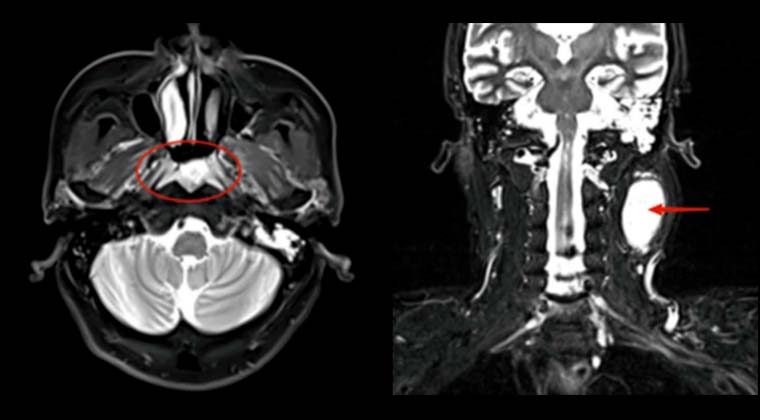

Пациент: мужчина, пожилого возраста

Рак легкого с метастазами в мозг, нарушение функции мозга, использует инвалидное кресло

До лечения: выраженный отёк вокруг опухоли и повышенное внутричерепное давление

После лечения: опухоль уменьшилась после 5 сеансов лучевой терапии

После лечения функция мозга восстановилась; пациент смог самостоятельно ходить

До лечения:

После лечения: